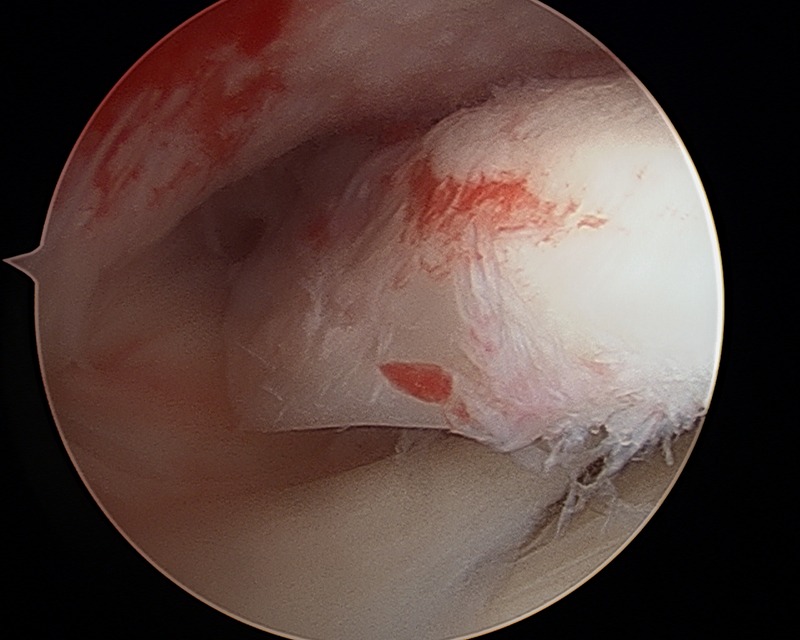

Chondral Defect

-

Chondral Fragment

Chondral Tibial Flap And Microfracture